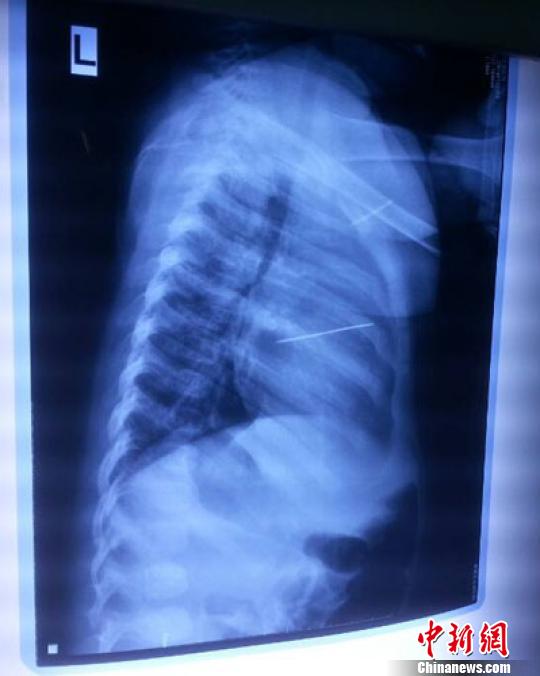

女?huà)胄仄崾拘呐K里面扎了一個(gè)縫衣針 蔡迅翔 攝

醫(yī)院胸心外科主任翟波介紹說(shuō),1月22日,小患者彤彤因?yàn)榘l(fā)燒抽搐來(lái)醫(yī)院就診,常規(guī)檢查時(shí)發(fā)現(xiàn)孩子心臟里面扎了一個(gè)縫衣針。

“第二天上午,我們做了個(gè)緊急彩超檢查,發(fā)現(xiàn)針是從患者右心室表面刺入,穿破室間隔,到達(dá)左心房,中間還有一部分損害到二尖瓣。于23號(hào)下午,我們就做了一個(gè)緊急手術(shù),手術(shù)中發(fā)現(xiàn),這枚針已經(jīng)刺入心臟,沒(méi)入了右心室的下面,表面已經(jīng)看不到針了,僅能看到一個(gè)小針眼,還在往外滲血,一點(diǎn)一點(diǎn)的滲,心包腔里面大概有100多毫升的出血,心包上一個(gè)洞,針在右心室表面刺入以后,穿過(guò)室間隔,在二尖瓣的上方,進(jìn)入了左心房,在針的四周,有很多纖維沉積物,包繞著這枚針。”翟波說(shuō),他們把針取出來(lái)以后,測(cè)量了一下,長(zhǎng)度大概是五厘米,同時(shí)發(fā)現(xiàn)這個(gè)針給患者左心房的后壁造成了一定的損傷,左心房的后壁已經(jīng)損傷了三分之二,還剩下有左心房的外膜,很薄的一層,如果這一層再破的話,這個(gè)孩子將會(huì)引起大出血,很快就會(huì)死亡。